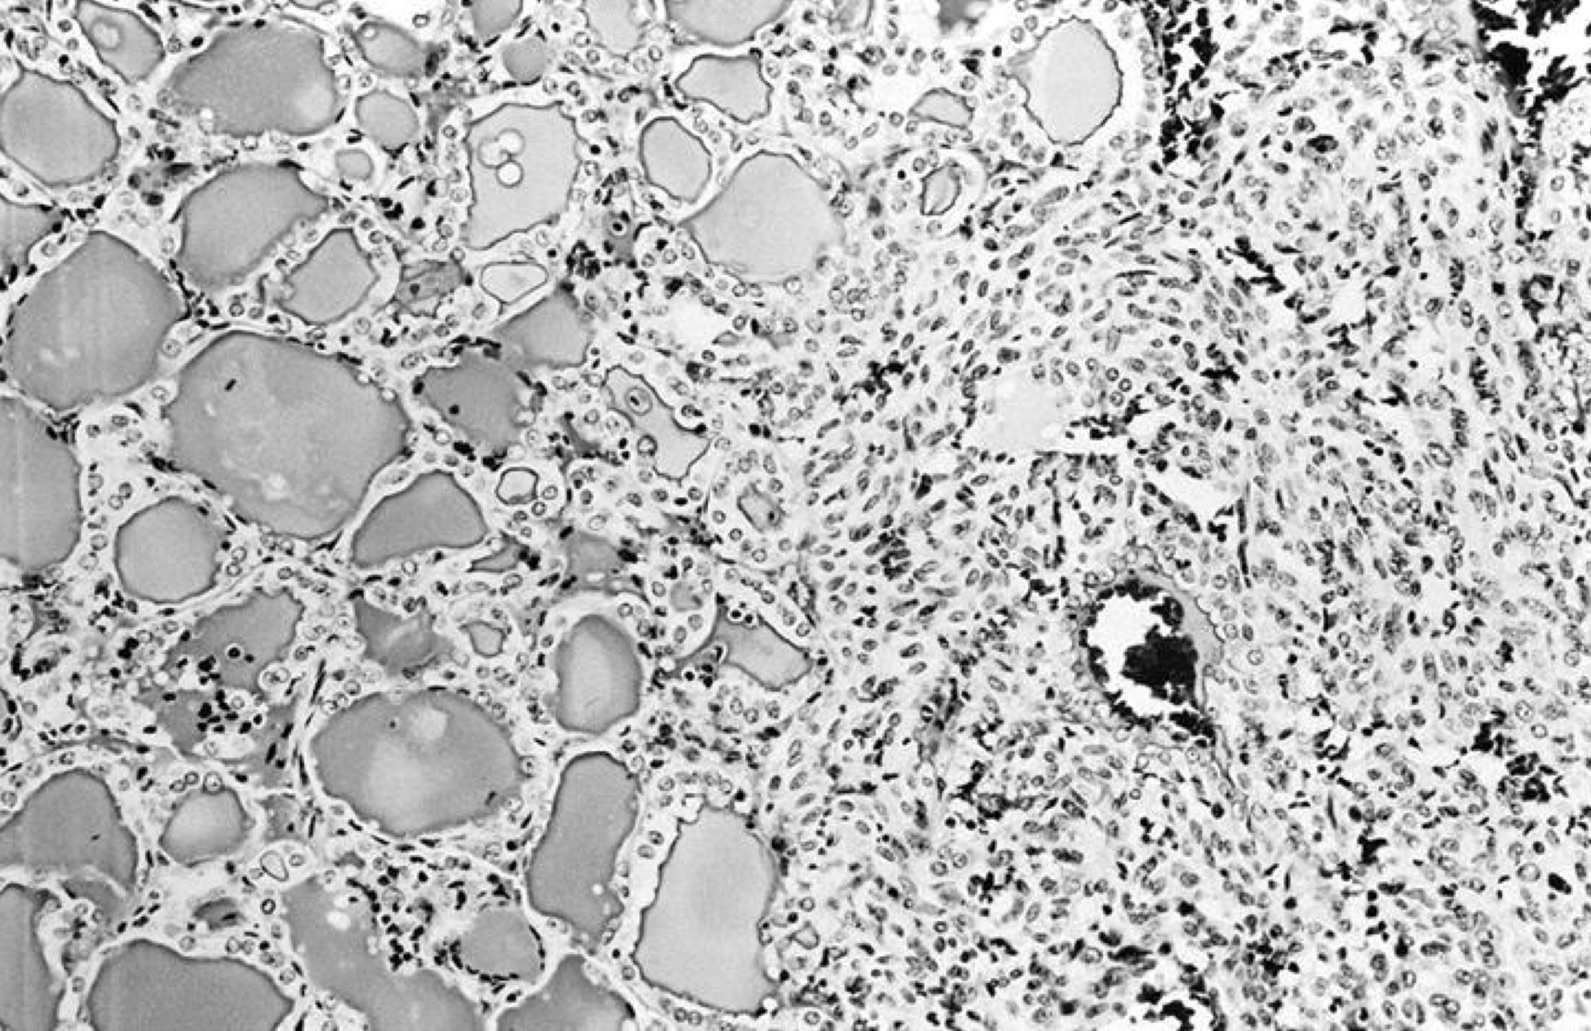

Microscopic (histologic) images

Contributed by Shipra Agarwal, M.D., Andrey Bychkov, M.D., Ph.D., Mark R. Wick, M.D., Asmaa Gaber Abdou, M.D. and AFIP

Patterns:

- Hyperfunctioning adenoma (Plummer adenoma): tall columnar epithelium, papillary infoldings, vacuolated cytoplasm, watery colloid showing scalloping

- Follicular adenoma with papillary hyperplasia: cystically dilated follicles, intraluminal papillae

- Focal papillary pattern, occasionally; especially in hyperfunctioning adenoma and follicular adenoma with papillary hyperplasia

- Cuboidal to low columnar cells

- Small round nuclei, smooth nuclear boundary, uniformly hyperchromatic or euchromatic, dense chromatin, absent nuclear features of papillary thyroid carcinoma, nuclear score 0 or 1 (JAMA Oncol 2016;2:1023)

- Inconspicuous nucleoli

- Rarely, lipid filled vacuoles in cytoplasm

- Mitoses are uncommon

- Scant stroma

- Secondary changes: fibrosis, hyalinization, hemorrhage, hemosiderin deposition, edema, cystic degeneration, calcification, osseous or cartilaginous metaplasia